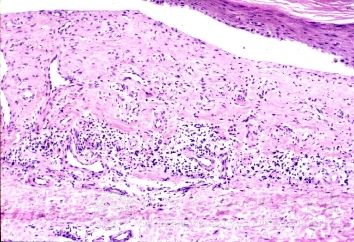

自体过敏性皮炎常突然泛发多数或群集性红斑、丘疹、丘疱疹及小水疱,可互相融合,泛发或对称分布。有时可有玫瑰糠疹样红斑,并可见沿搔抓部呈平行线状排列丘疱疹、水疱,自觉瘙痒剧烈。从原发皮损至全身泛发一般需经7~10天左右。